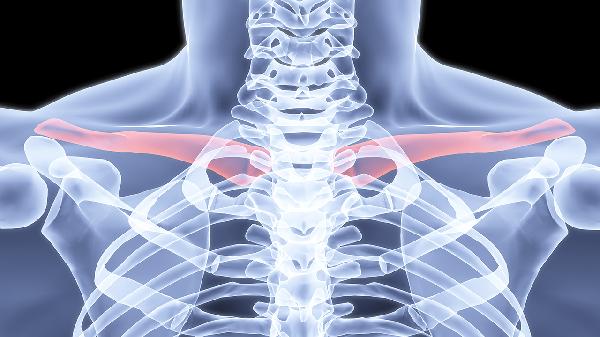

伤后2周开始肩关节钟摆训练,4周后逐步进行被动抬臂练习,角度控制在30°内递增。过早负重训练可能造成二次损伤,延迟康复进程。